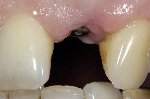

- Komplette Regeneration der Pappille 3 Monate nach der Eingliederung der Implantatkrone

- Vollkeramische Restauration auf Implantat